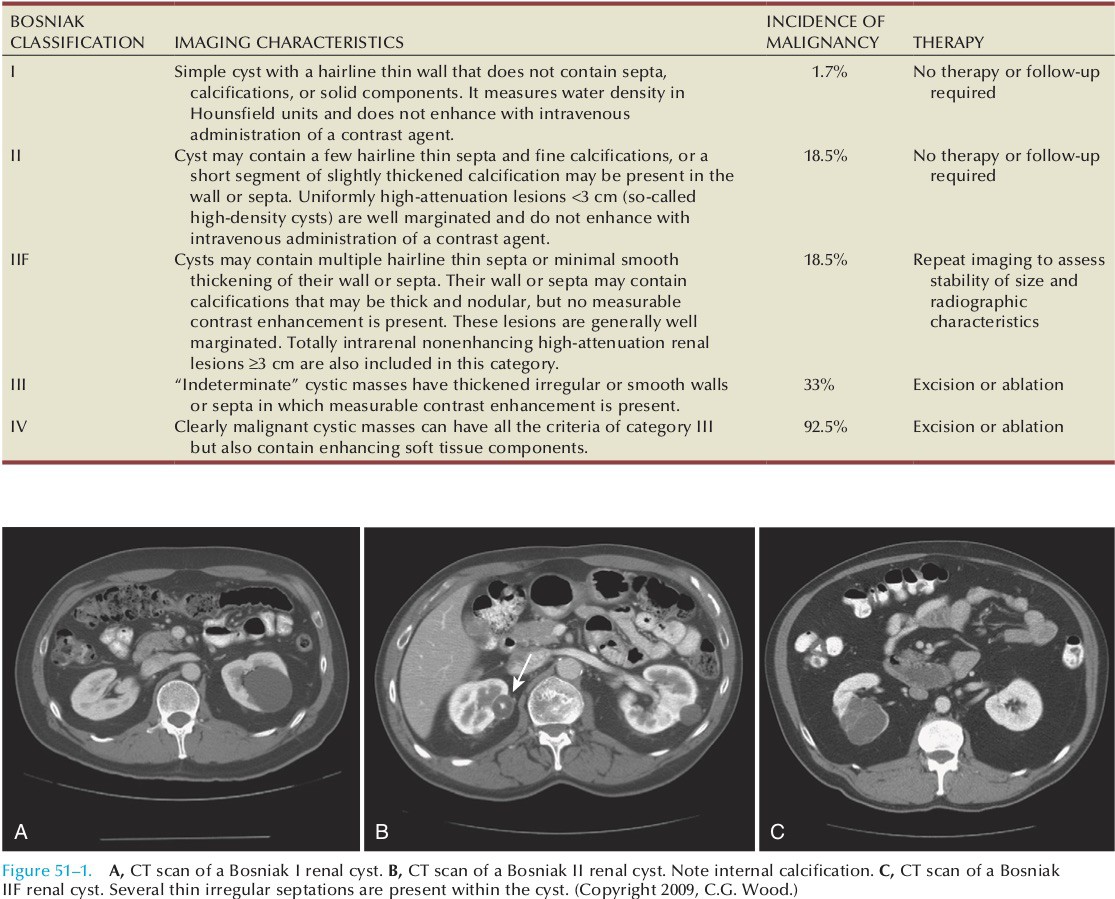

Киста почки может быть простой (I Bosniak) и сложной (II, IIF, III и IV Bosniak). Простые могут образовываться в почках на любом возрастном этапе. Отличаются наличием одной камеры, которая заполнена жидкостью. Вероятность ее преобразования в рак крайне мала. Сложные характеризуются перечисленными ранее симптомами, отличаются высоким риском озлокачествления.

Bosniak-I

При прохождении МРТ или КТ четко видна ее однокамерность. Категорию составляют простые кисты. Часто образуются в почках, но при этом не являются угрозой. Как правило, характеризуется тонкой перегородкой. Стенки без утолщений и отложений солей. Формации этой категории не требуют дальнейшего наблюдения или лечения, поскольку являются доброкачественными.

Bosniak-II

Сюда относятся несложные кисты. В отличие от предыдущей группы возможно небольшое утолщение стенок, а также наличие незначительных кальцификатов. При обследовании может быть выявлено несколько тонкостенных перегородок. Группу также составляют плотные образования с четкими контурами размером меньше 3 см. Являются доброкачественными, лечения не требуют.

Bosniak-IIF

Уплотнения характеризуются увеличением полости, утолщением стенок между перегородками, возможны узелковые отложения кальция на них. При обследовании вводимый контраст не виден. Кисты однородной плотности и размерами больше 3 см также входят в эту категорию. Они еще попадают под признаки доброкачественности, но уже требуют наблюдения. Малый процент таких образований числится раковыми.

Bosniak-III

Образования с неравномерными утолщениями стенок и перегородок, отложения кальция неравномерны. При обследовании может незначительно накапливаться контраст. Сюда входят те опухоли, которые тяжело однозначно отнести к злокачественным или доброкачественным. В любом случае требуется наблюдение и операция, так как половина случаев — раковые наросты.

Bosniak-IV

Однозначно раковое образование. Все признаки злокачественности присутствуют: четко видно накопление контраста, перегородок много, с утолщенными стенками, крупными узелковыми отложениями кальция. Сами полости заполнены жидкостью с неровным контуром. Требуют немедленного хирургического вмешательства для предотвращения развития кистозного рака.